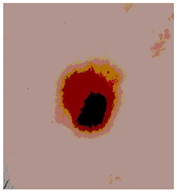

![]() | ![]() | ![]() | ![]() |

| Img1 | --- Pixel Intensity (0–255) ---> | ||

| Original Image | Th2 | Th3 | Th4 | Th5 |

|---|---|---|---|---|

![]() Img1 | ![]() | ![]() | ![]() | ![]() |